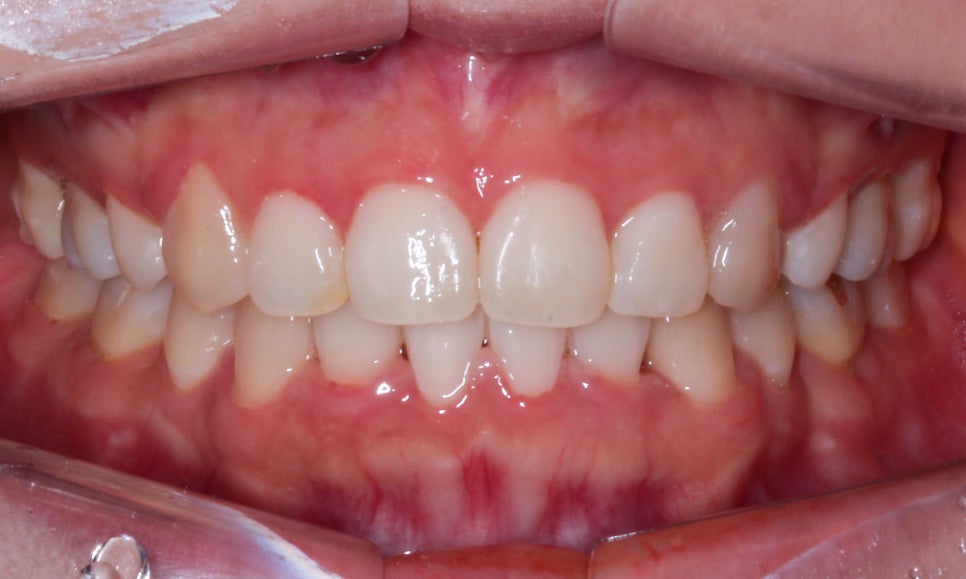

송곳니덧니 case의 교정 후 모습입니다.

치아의 정면 구내사진을 보면 교정 전

송곳니의 위치가 주변 치아보다 상당히 높게

맹출된 모습을 확인할 수 있었는데요,

교정 후 이러한 high canine 증상이

사라지면서 전치부의 스마일라인이

확연하게 정돈된 느낌으로 바뀌었습니다.